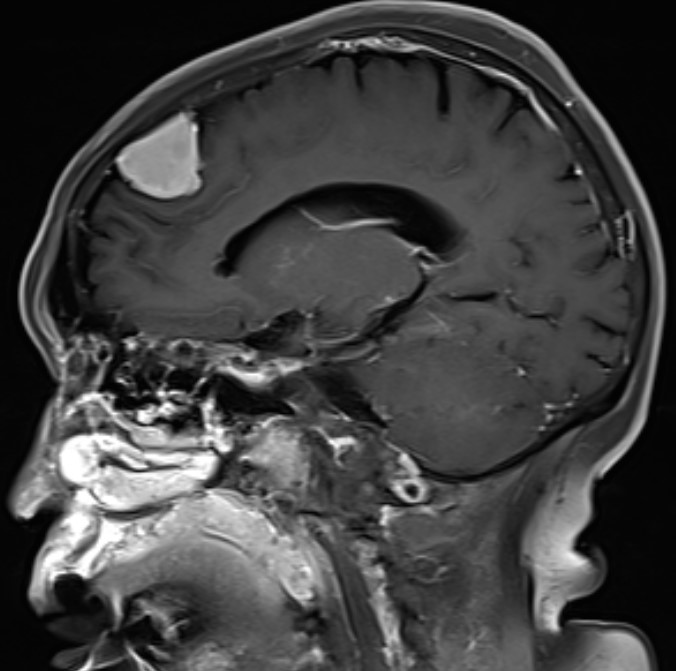

患者女性,62岁,因头晕一月在外院检查头部MR发现左额镰窦旁肿瘤来我院

完善术前检查在全麻下行左额开颅肿瘤切除术